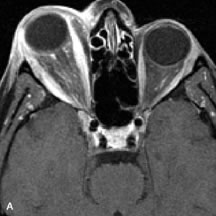

On MRI, uveal melanomas have a typical appearance that helps to differentiate them from other primary and secondary intraocular tumors as well as choroidal detachments. Pigmented melanomas are hyperintense on Tl-weighted images, hypointense on T2-weighted studies, and hyperintense on proton density–weighted examinations (Fig. 24).30,31,50,80–82 These signal characteristics have been attributed to the paramagnetic properties of melanin because of stable free radicals that shorten the T1 and T2 relaxation times. Moderate enhancement is seen on postgadolinium T2-weighted images. Gadolinium-enhanced T1-weighted images are particularly sensitive in detecting choroidal melanomas.83 MRI may be less sensitive in detecting extrascleral extension of tumor than echography performed by an experienced ultrasonographer.84

Fig. 24. A. T1- and (B) T2-weighted MR scans demonstrate a small nodular intraocular mass (arrows) that is very hyperintense on the T1-weighted scan and hypointense on the T2-weighted image. This signal intensity pattern is due to the presence of free radicals within melanin granules. C and D. Postcontrast fat-suppressed T1-weighted scans demonstrate homogeneous intense enhancement of the lesion and no evidence of seleral penetration or optic nerve invasion.